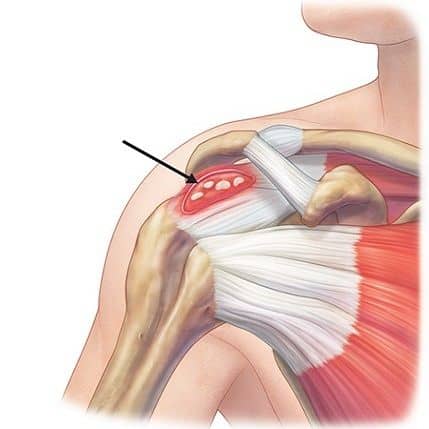

– Khớp gối là một khớp bản lề, lớn nhất cơ thể, nằm ngay dưới da, bao gồm đầu dưới xương đùi, đầu trên xương chầy và xương bánh chè. Các thành phần này được kết nối với nhau bởi hệ thống các dây chằng, bao khớp, trong đó quan trọng nhất là dây chằng chéo trước và dây chằng chéo sau. Hai dây chằng này giữ cho đầu trên xương chầy và đầu dưới xương đùi không bị trượt theo chiều trước sau khi khớp gối vận động.

– Ngoài ra hệ thống dây chằng bên trong và dây chằng bên ngoài giữ cho gối không bị trượt sang bên. Lót giữa lồi cầu đùi (hình cầu) và mâm chầy (phẳng) là sụn chêm trong và sụn chêm ngoài, làm gia tăng diện tiếp xúc, phân bố đều lực tác động lên gối.

– Khớp gối bao gồm phần dưới của xương đùi và phần trên của xương chày (được gọi là mâm chày), đầu trên xương mác và xương bánh chè. Đầu xương được bọc bởi lớp sụn khớp. Một lớp sụn đệm vào giữa chúng gọi là sụn chêm trong (hình chữ C) và một lớp sụn bên ngoài gọi là sụn chêm ngoài (hình chữ O).

– Hai đầu xương được giữ lại với nhau bằng các dây chằng, ở hai bên là dây chằng trong và dây chằng ngoài, ở trung tâm khớp là dây chằng chéo trước và dây chằng chéo sau. Xương bánh chè là một xương vừng, nó nằm ở dưới gân cơ tứ đầu đùi và có vai trò bảo vệ gân tứ đầu cũng như tăng cánh tay đòn của gân này.